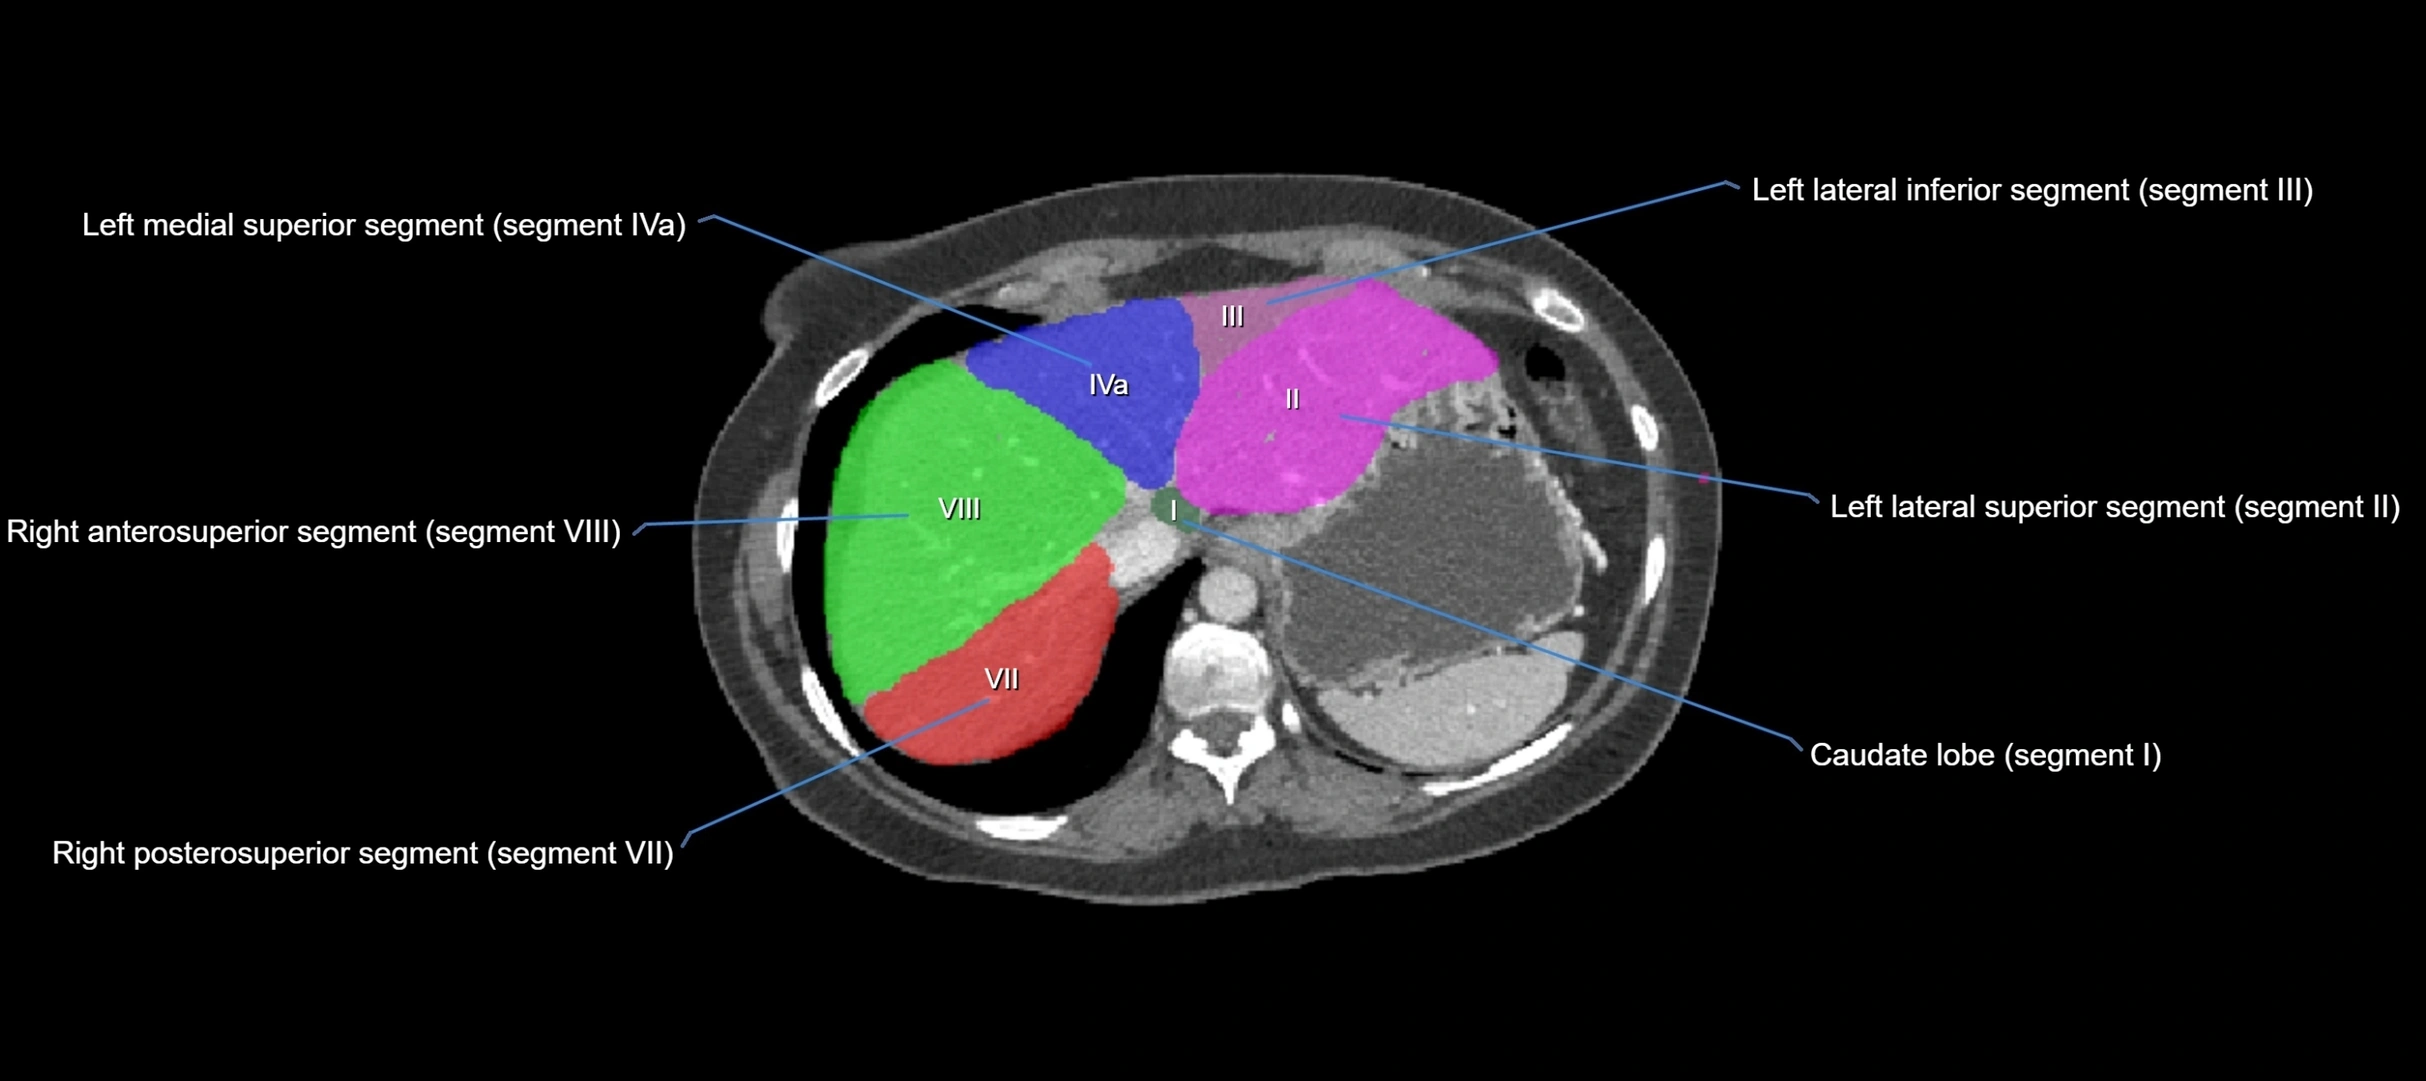

The caudate lobe of the liver is a distinct anatomical subdivision of the liver, designated as segment I in Couinaud’s classification. It lies on the posterior surface of the liver, between the fissure for the ligamentum venosum (left boundary) and the groove for the inferior vena cava (IVC) (right boundary). Superiorly, it is related to the posterior liver surface, and inferiorly it is separated from the left lobe by the porta hepatis.

The caudate lobe is unique because it receives dual portal venous and arterial inflow from both the right and left portal veins and hepatic arteries. It also has independent venous drainage directly into the IVC via multiple small hepatic veins, unlike other lobes that drain through the three main hepatic veins.

This anatomical autonomy makes the caudate lobe especially significant in liver surgery, transplantation, and hepatic venous outflow obstruction syndromes (e.g., Budd–Chiari syndrome). Enlargement of the caudate lobe is a characteristic imaging feature in chronic liver disease and cirrhosis.

CT Appearance

CT Pre-Contrast:

• Caudate lobe appears as a soft-tissue density, isodense to the rest of the liver

• Enlargement may be appreciated in cirrhosis or Budd–Chiari syndrome

CT Post-Contrast:

• Homogeneous enhancement in the portal venous phase, similar to rest of liver

• Independent venous drainage into the IVC may be visualized

• Lesions follow characteristic CT enhancement patterns (HCC: arterial hyperenhancement with washout; hemangiomas: peripheral nodular enhancement with centripetal fill-in)

CT Venous Phase (functional significance):

• Caudate lobe often enhances relatively more than other lobes in Budd–Chiari syndrome, due to preserved venous outflow

CT Image

image